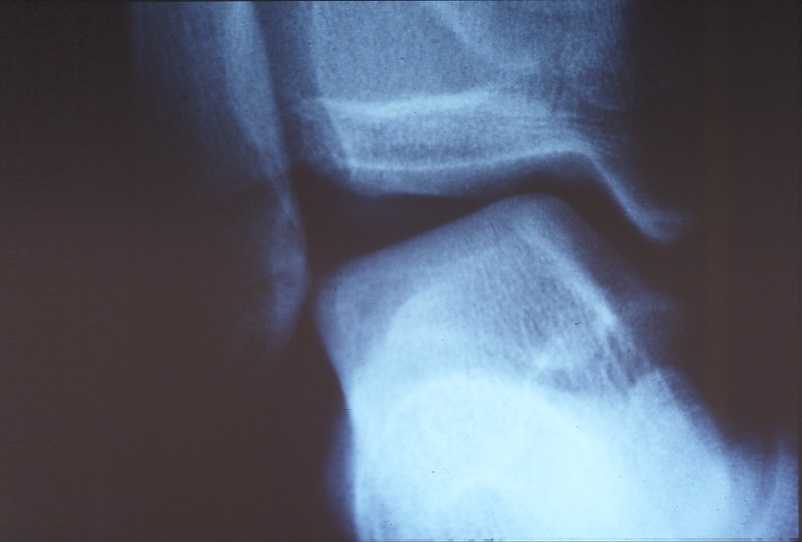

X-rays can be used to check for fractures, to check for spicules, to perform a stress X-ray to check for ligament loosening (Photos 3 and 4). Lately, MRI and ultrasound examination are adopted to diagnose in detail.

Photo 3: The ankle is preserved at a glance

Photo 4: The same ankle in the stress